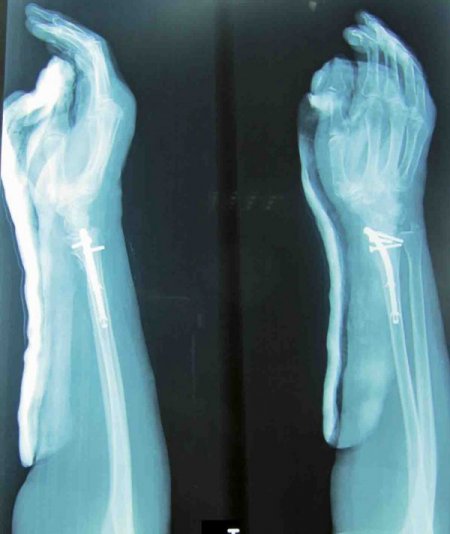

Sol ön kol kırığı (colles kırığı) nedeniyle polikliniklerine başvuran İsmihan Demirel adlı hastaya, yeni bir teknik olan kapalı intramedüller (ilik içi çivi) uygulaması yapılarak kırık tespitinin sağlandığını belirten Opr. Dr. Taşkoparan, “Daha önceden bu tür ameliyatlar açık cerrahi ile yapılıyor, plakla tespit edilerek 1 ay alçı tedavisi uygulanıyordu. Kemik erimesi olan hastada bu eski yöntem, kırılan bölgede eklem sertlikleri ve ağrı meydana getirerek fizik tedavi uygulamalarını zorunlu kılıyordu.” diye konuştu.

Taşkoparan, ilik içi çivi uygulaması tekniği ile yapılan kapalı ameliyatlarda ise kırık bölgesinde 1-2 gün duran alçı çıkarıldığı için kemik erimesine bağlı eklem şişliği ve hareket kısıtlılığı ortadan kalktığını, hastanın erkenden sosyal yaşamına dönebildiğini vurguladı. CİHAN